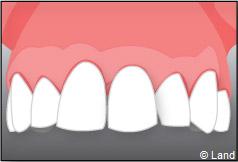

Exemple d’un implant unitaire pour remplacer une dent antérieure manquante.

Situation clinique terminée